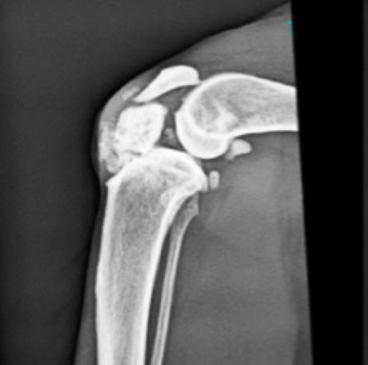

고양이 무릎 관절낭 내부에 양성 골종양이 생긴 증례이다.

딱 봐도 겁먹을 정도로 거대한 뼈조각 증식이 보인다.